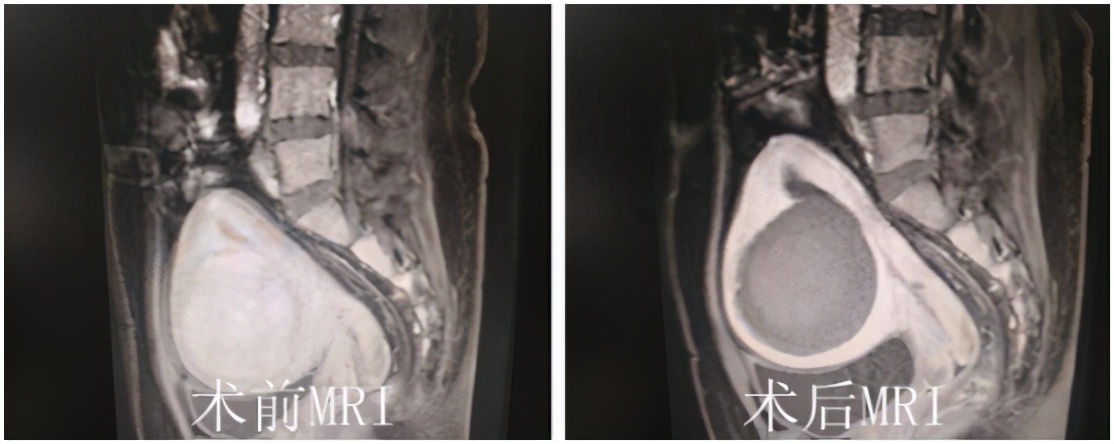

事实:应用海扶刀®设备治疗子宫肌瘤对于肌瘤的大小没有特别的限制,只要海扶刀®机载超声定位能够看得见的、能够建立安全超声治疗通道的,通常都能够进行消融治疗。几公分,十几公分,甚至二十几公分的肌瘤海扶刀®设备都可以治疗,并且一般是一次性消融治疗,只有极少数肌瘤特别大的情况可能需要分次消融治疗。

(子宫肌瘤145*120*102mm,应用海扶刀®设备一次性消融治疗)